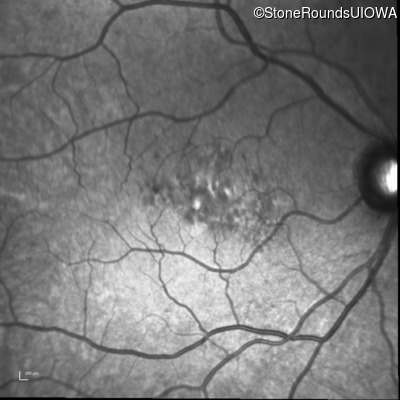

Infrared Fundus Photograph - Left - 20/40 -2

Exemplar